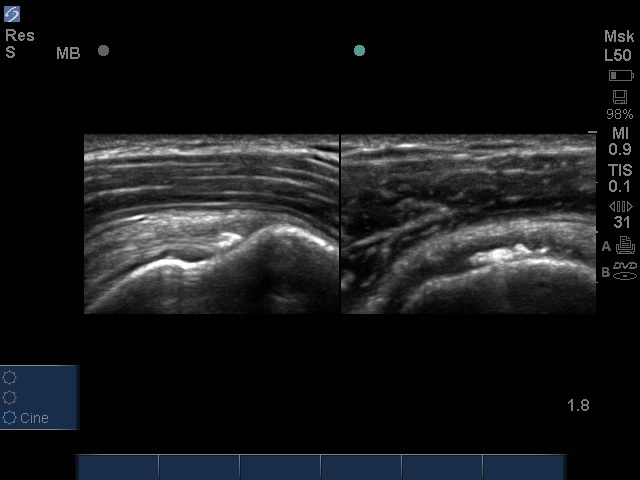

Cette image illustre une tendinite calcifiée du muscle sus-épineux.